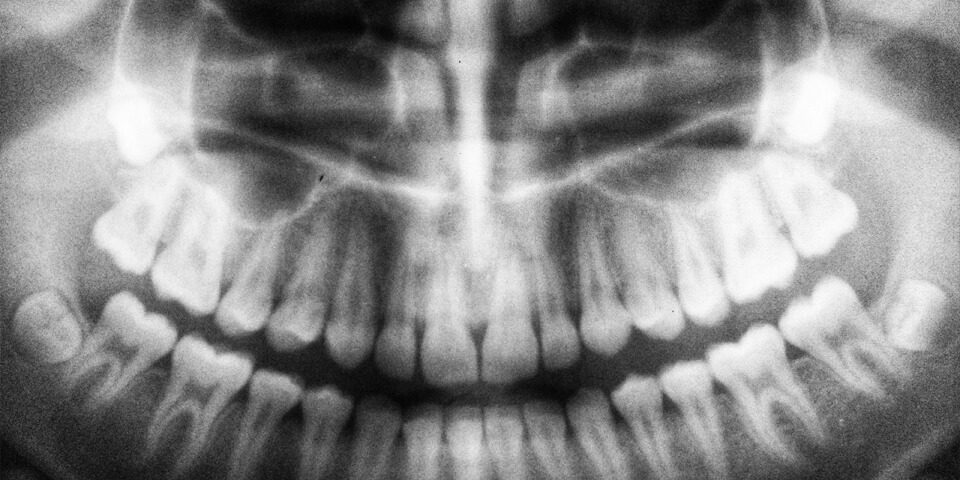

Questi elementi dentali vengono chiamati “del giudizio” poiché compaiono approssimativamente tra i 17 e i 25 anni, età in cui si è portati a essere più maturi e responsabili. Non sono rari, tuttavia, casi di iperdentia o opodontia, ovvero quei casi in cui i denti del giudizio sono più o meno di quattro. È inoltre possibile che i denti del giudizio non compaiano mai perché totalmente assenti, oppure che rimangano sotto le gengive, senza la possibilità di essere visti se non con una panoramica o che spuntino solo in parte, rimanendo a metà.

Per riconoscere il dente del giudizio è opportuno individuare i terzi molari, ossia quelli collocati nella parte più interna delle quattro semi-arcate dentali. Un’altra caratteristica dei denti del giudizio è che sono gli ultimi a comparire, perché generalmente emergono tra i 18 e i 25 anni.

È proprio in virtù della loro coloro comparsa tardiva che hanno preso tale nome. Se, nella maggior parte dei casi, è per il paziente piuttosto facile individuare qual è il dente del giudizio, è altrettanto comune che questi elementi dentali non emergano mai o che emergano solo in parte. Tutte queste situazioni andrebbero verificare e valutate dall’Odontoiatra, perché potrebbero portare all’insorgenza di infiammazioni croniche e situazioni di disagio per il paziente.